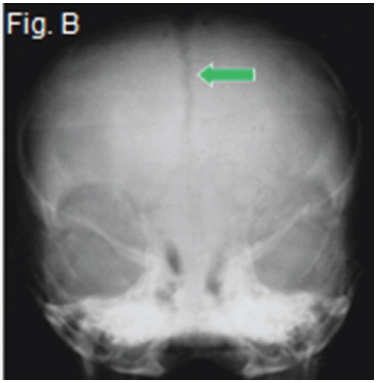

A diagnosis of frontonasal malformation was made. Frontonasal malformation has been defined as a combination of two or more of the following characteristics: hypertelorism, broadened nasal bridge, medium facial cleft affecting the nose and the upper lip and sometimes the palate, unilateral or bilateral clefting of the nasal alae, lack of formation of the nasal tip. The appearance of cranium bifidum (also known as cleft skull or enlarged parietal foramina) is characterized by the unsuccessful midline migration of the cranial vault, and a V-shaped hairline prolongation onto the middle of the forehead. The clinical picture (Fig. A) shows many of the characteristics mentioned above. The postero-anterior view of frontonasal malformation (Fig.B) shows hypertelorism, a widened nasal bridge and persistence of the metopic suture (arrow). A further postero-anterior view (Fig. C) shows persistence of the anterior fontanelle and a widened nasal bridge (arrow) with concomitant hypertelorism. The Waters view (Fig.D) demonstrates the hypoplastic maxillary sinuses. There is also marked hypertelorism and a widened nasal bridge.